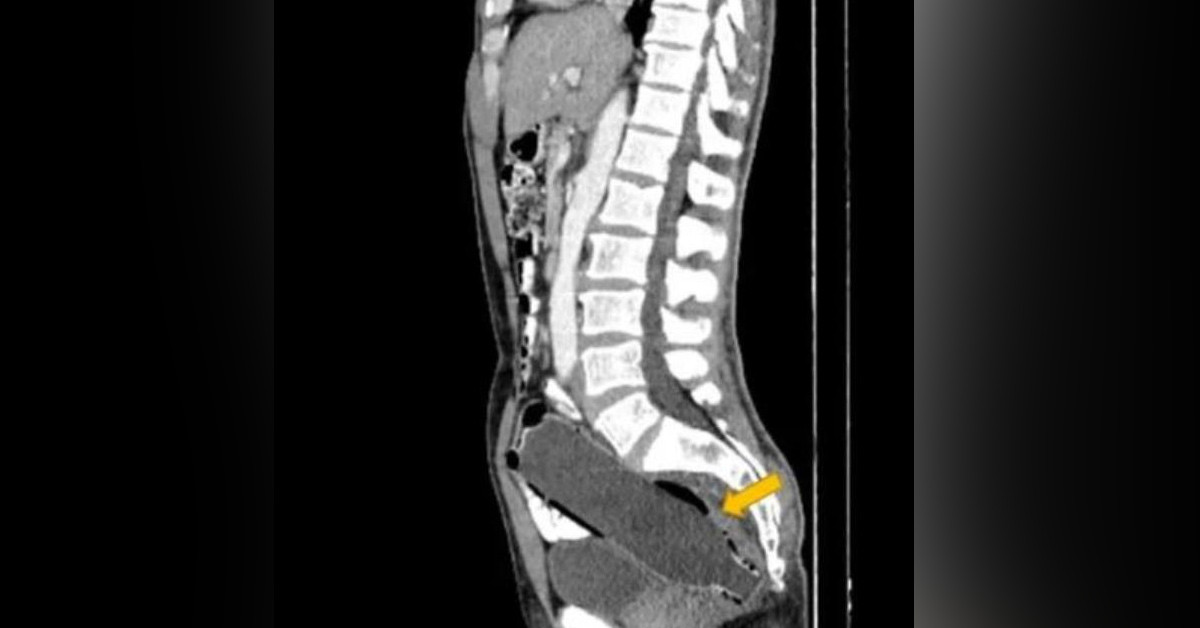

İsmi belirtilmeyen 50 yaşında bir adam 3 gün boyunca tuvalete çıkamamasından sonra eşiyle birlikte hastaneye gitti. Adamı muayene etmeye başlayan doktorlar, muayene esnasında bir sorun göremedi. Adamın başka bir şikayeti olmadığı için röntgen filmi istedi. Röntgen filmi çekildikten sonra gerçek ortaya çıktı.